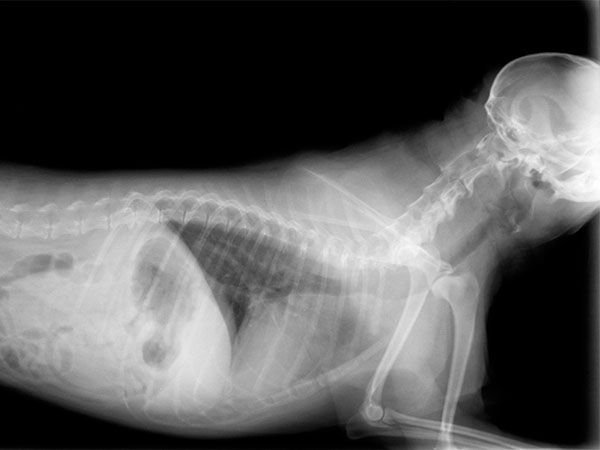

An ultrasound examination, also known as ultrasonography, is a non-invasive imaging technique that allows internal body structures to be seen by recording echoes or reflections of ultrasonic waves. Ultrasound equipment directs a narrow beam of high frequency sound waves into the area of interest.

The ultrasound waves are converted into an image that is displayed on the monitor, giving a 2-dimensional “picture” of the tissues under examination. The technique is invaluable for the examination of internal organs and is very useful in the diagnosis of cysts and tumors.